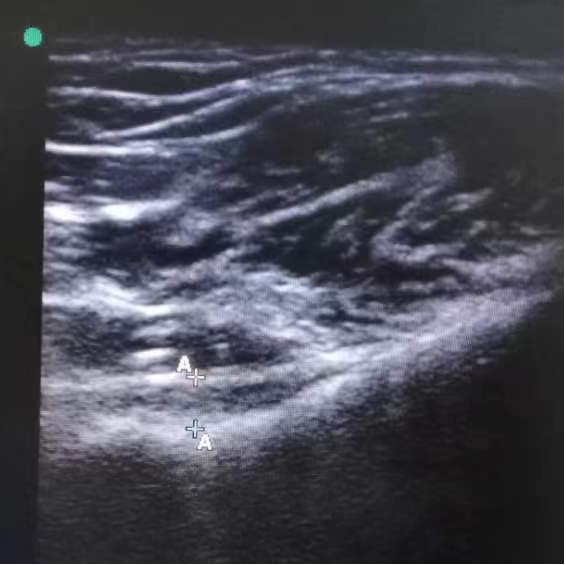

特色技术:超声引导下肩关节囊液压扩张手法松解术

超声引导下肩关节囊液压扩张手法松解术是一种结合超声影像实时引导与液压扩张原理的微创治疗技术,主要用于粘连性肩关节囊炎的治疗。

1. 超声引导精准定位

高频超声探头可清晰显示肩关节囊的结构,动态监测穿刺针位置,确保液体精准注入目标区域,避免损伤血管、神经及肌腱。